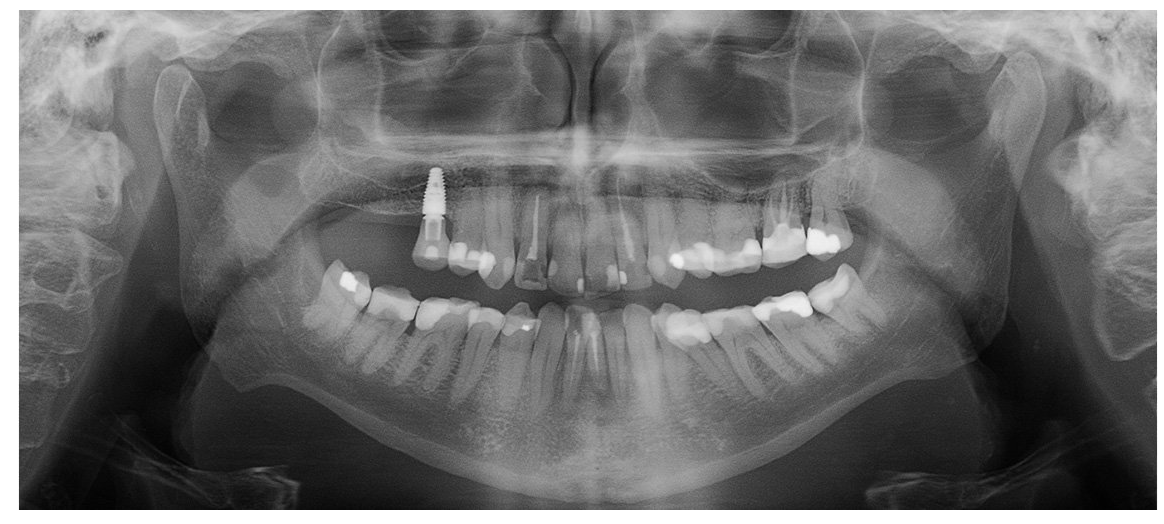

Obrazowanie 2D z czujnikiem 3D

Nie ma potrzeby przełączania się między obrazowaniem CBCT i panoramicznym, ponieważ zaawansowany system obrazowania SmartPan™ wykorzystuje ten sam czujnik 3D, który wytwarza obrazy 2D. Zdjęcia panoramiczne można łatwo przeglądać i wybierać do diagnozy.